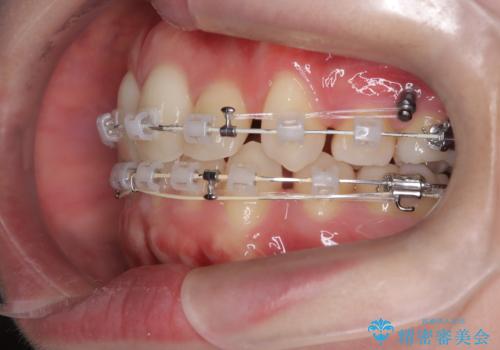

上下4本の抜歯と審美ワイヤー矯正で整った歯並びへ

- 患者様は、歯並びの乱れを整えたいとのことで来院されました。診察の結果、歯列のスペース不足が原因で前歯のガタつきが目立ち、噛み合わせにも影響が出ている状態でした。歯を正しく並べるためにはスペースの確保が必要と判断し、上下の小臼歯4本を抜歯して、審美ワイヤー矯正(白いワイヤーと透明ブラケット)で治療を行う計画を立てました。

まず、抜歯によって歯を動かすためのスペースを確保。その後、審美ワイヤー矯正を用いて、前歯のガタつきを整えながら、噛み合わせの調整も行いました。審美装置を使用することで、矯正中も目立ちにくく、自然な仕上がりを目指して治療を進めました。治療の結果、歯並びがきれいに整い、口元のバランスも改善しました。患者様からは「歯並びがきれいになり、自信を持って笑えるようになった」と喜びの声をいただきました。